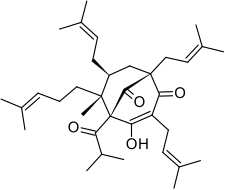

Chemistry

Hyperforin is a prenylated phloroglucinol derivative and is a member of the Polycyclic polyprenylated acylphloroglucinol family, also known as the PPAP family. Hyperforin is a unique PPAP because it consists of a C8 quaternary stereocenter which was a synthetic challenge unlike other PPAP synthetic targets.[3][4][10] The structure of hyperforin was elucidated by a research group from the Shemyakin Institute of Bio-organic Chemistry (USSR Academy of Sciences in Moscow) and published in 1975.[11][12] A total synthesis of the non-natural hyperforin enantiomer was reported in 2010 which required approximately 50 synthetic transformations.[13] In 2010, an enantioselective total synthesis of the correct enantiomer was disclosed. The retrosynthetic analysis was inspired by hyperforin's structural symmetry and biosynthetic pathway. The synthetic route undertaken generated a prostereogenic intermediate which then established the synthetically challenging C8 stereocenter and facilitated the stereochemical outcomes for the remainder of the synthesis.[10]

Hyperforin is unstable in the presence of light and oxygen.[14] Frequent oxidized forms contain a C3 to C9 hemiketal/heterocyclic bridge or will form furan/pyran derivatives.[7][8]